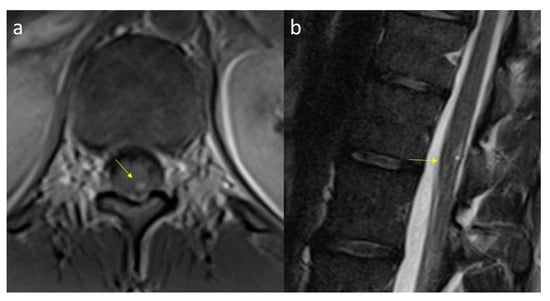

2. Case Report